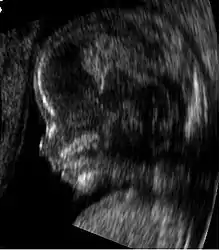

Modern 3D ultrasound images provide greater detail for prenatal diagnosis than the older 2D ultrasound technology.[6] While 3D is popular with parents desiring a prenatal photograph as a keepsake,[7] both 2D and 3D are discouraged by the FDA for non-medical use,[8] but there are no definitive studies linking ultrasound to any adverse medical effects.[9] The following 3D ultrasound images were taken at different stages of pregnancy:

Fetus at 17 weeks